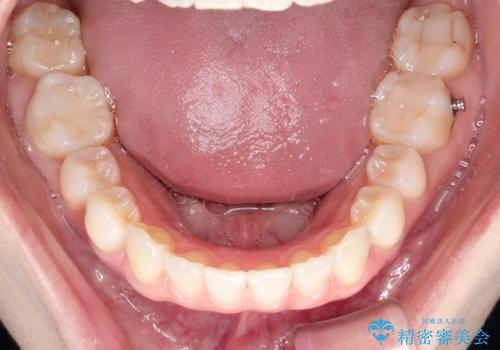

インビザラインによる矯正治療 前歯を整った歯並びへ

- 1年2ヶ月

インビザラインを使用して矯正することとしました。